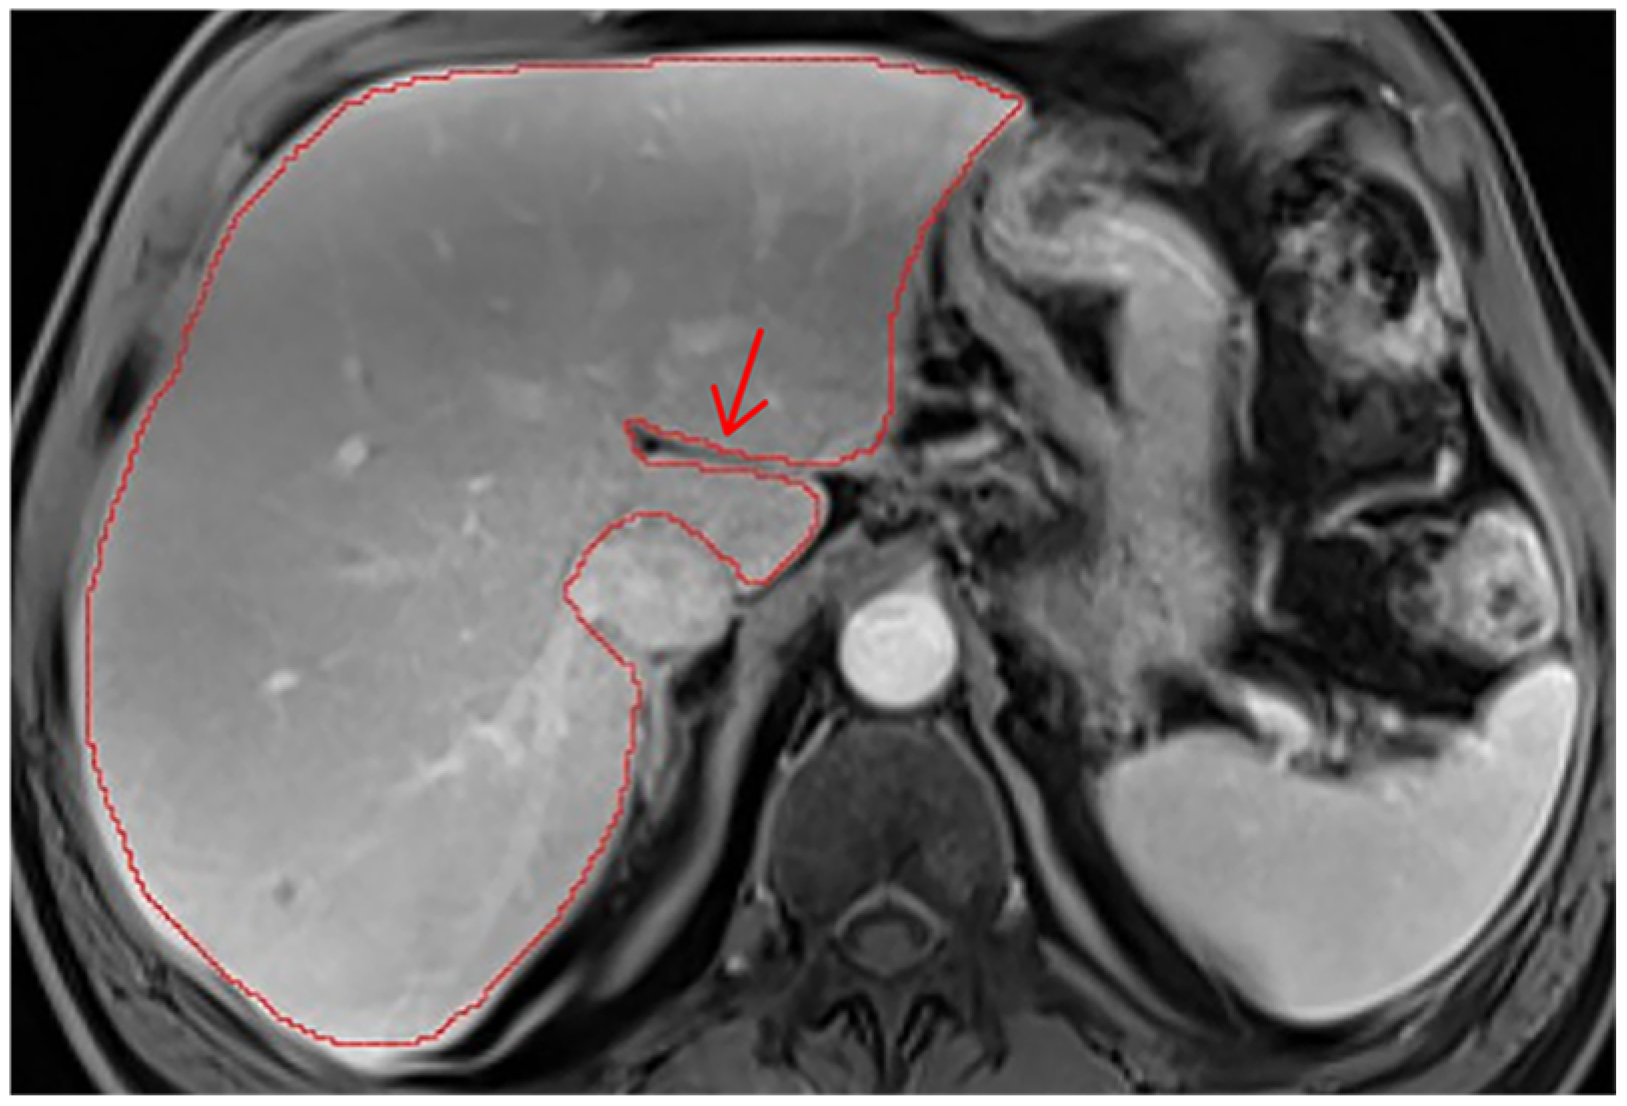

Appendix A.2. Hepatic Hilum Segmentation